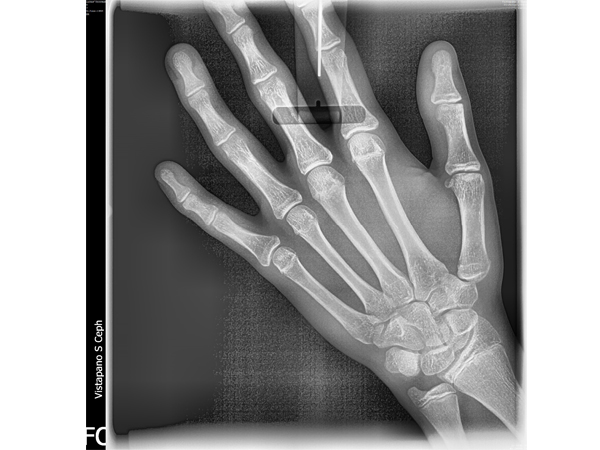

Con el nuevo VistaPano S Ceph se consiguen rápidas tomas tele radiográficas con una extraordinaria calidad de imagen – y esto con unas dosis de exposición lo más reducida posible. La razón son los breves tiempos de escaneado que requieren los sensores lineales, solo 4,1 segundos, y que reducen drásticamente el riesgo de que se produzcan imágenes borrosas debidas al movimiento del paciente. Precisamente con niños, en el campo de la ortodoncia, esta combinación de dosis radiográfica reducida y breves tiempos de escaneado representa una ventaja considerable. Dado que ya están integrados en el aparato dos sensores High-End-CsI para las radiografías panorámicas y la función cefalográfica, se elimina el largo cambio de conexión del sensor , y así el riesgo de sufrir averías. Todo esto convierte a VistaPano S Ceph en la solución radiográfica ideal para la ortodoncia, la cirugía oral y maxilofacial. Además, VistaPano S Ceph le ofrece todas las funciones y ventajas de VistaPano S.